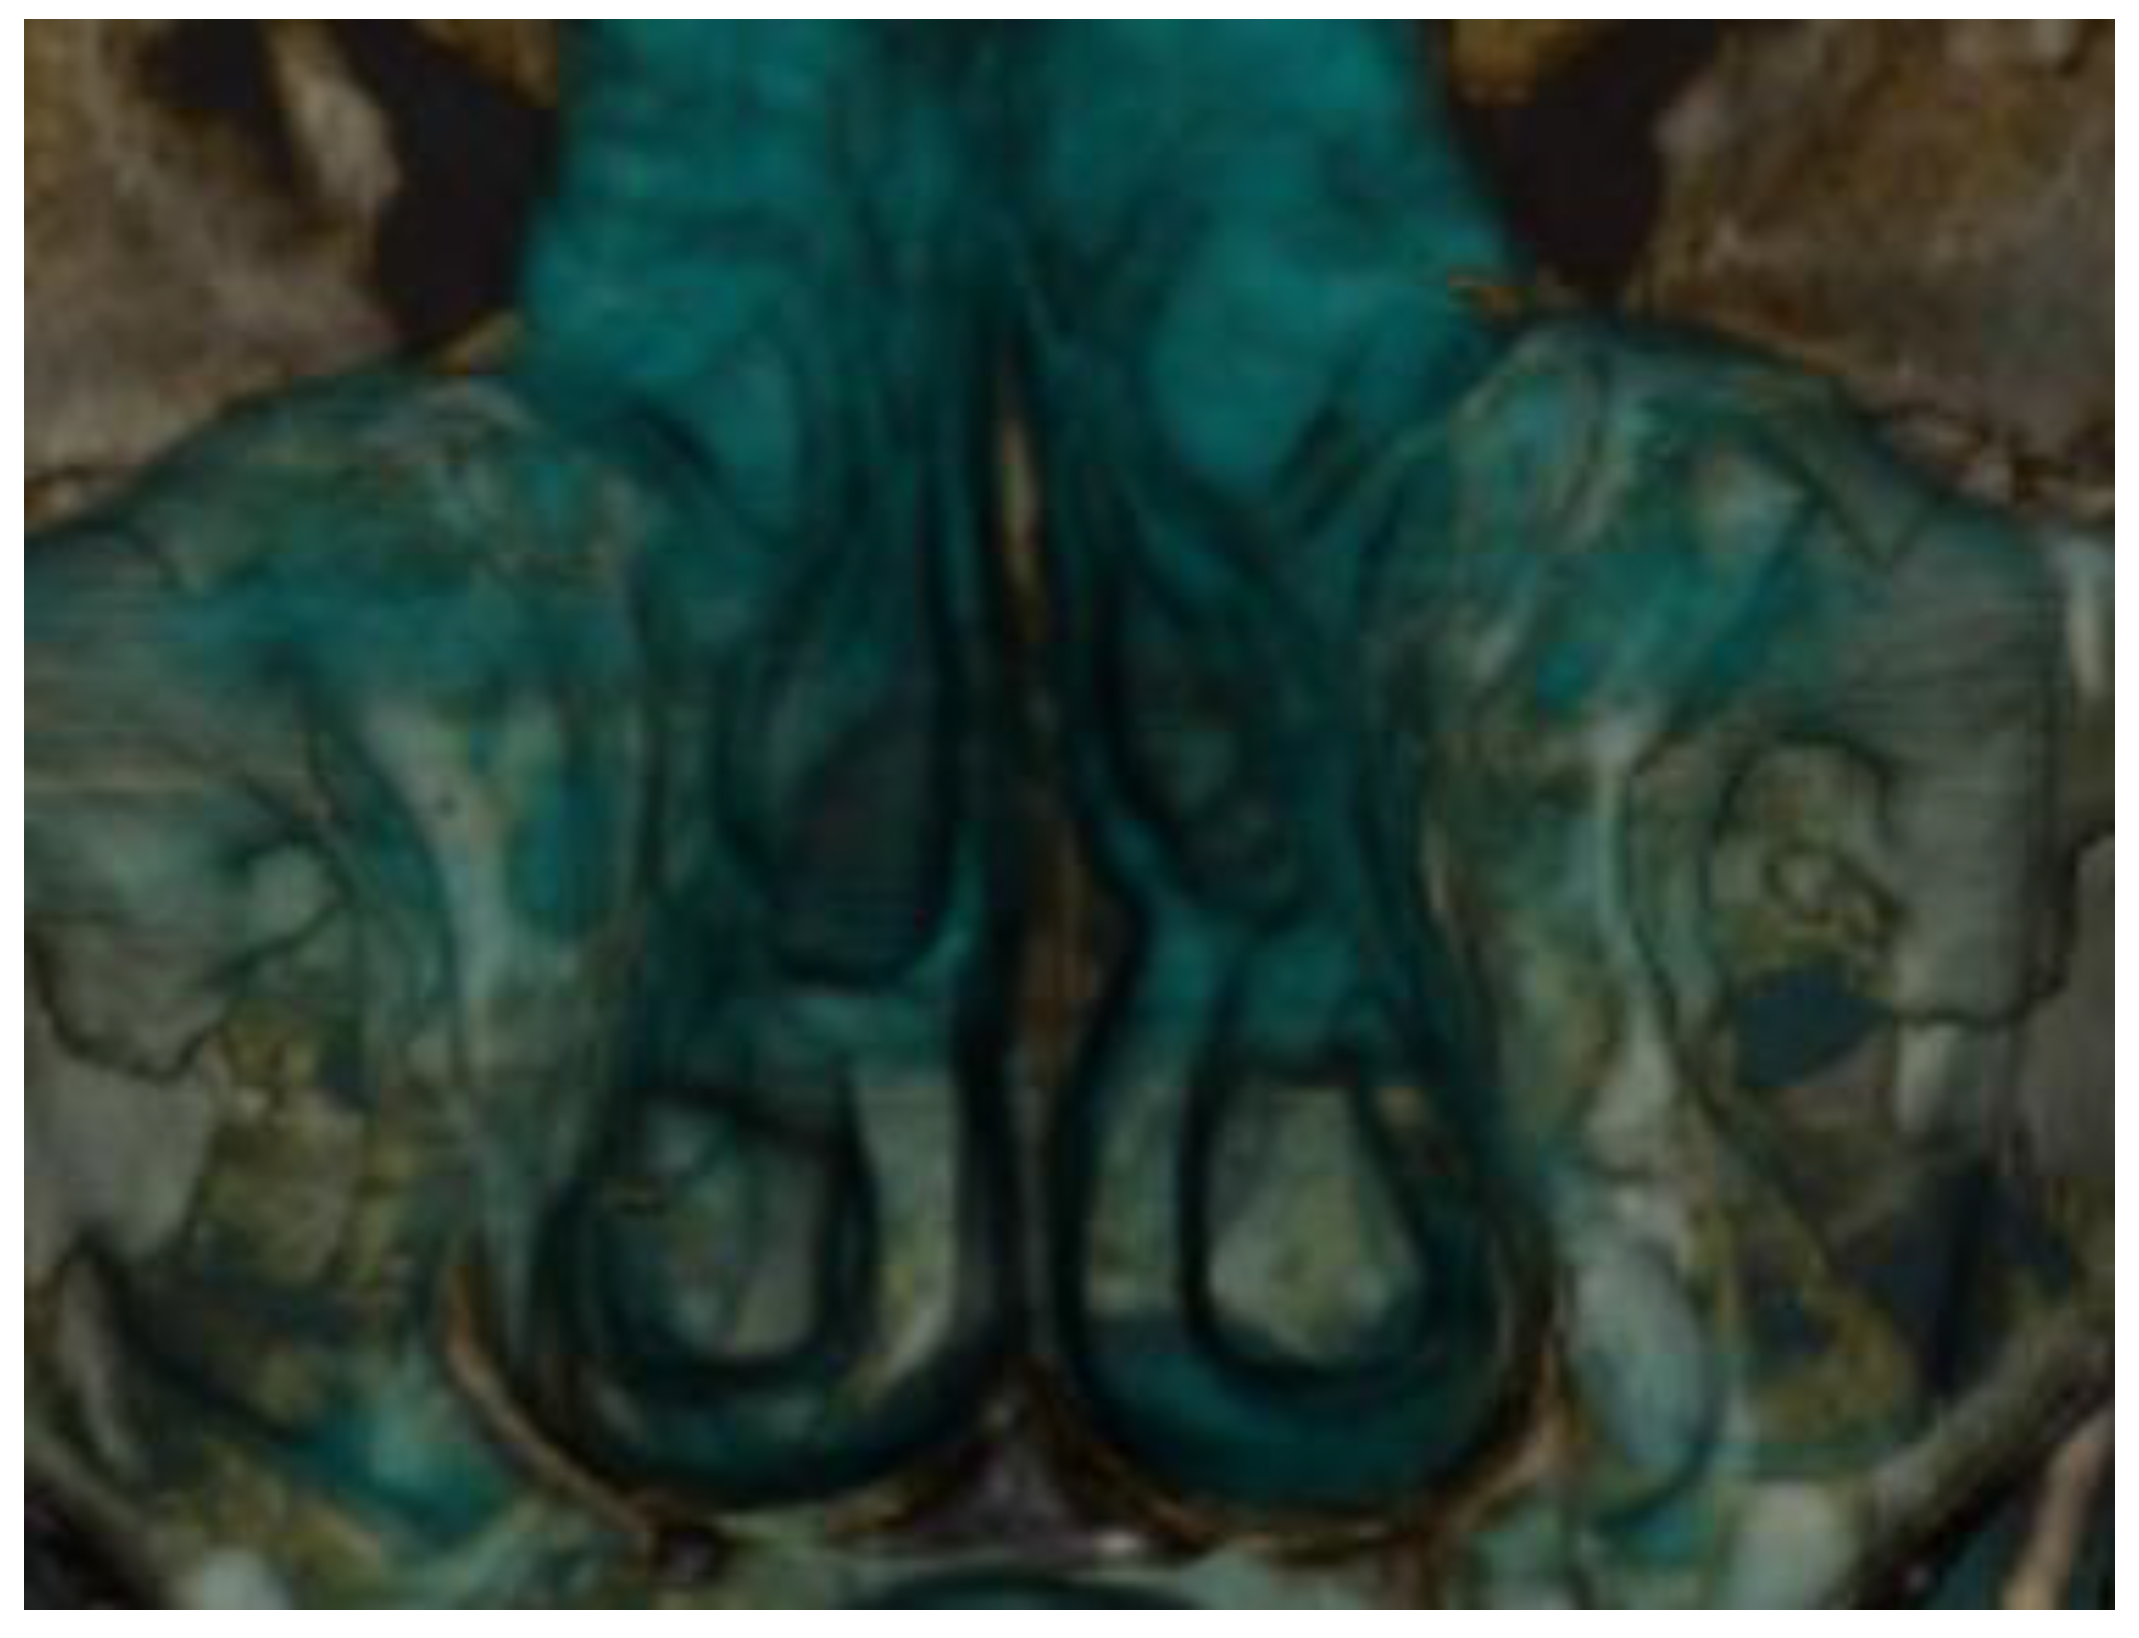

Maxillary Sinus